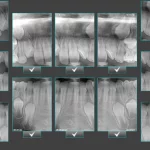

3 Key Differences Between Extraoral Dental Bitewings and Intraoral Dental Bitewings